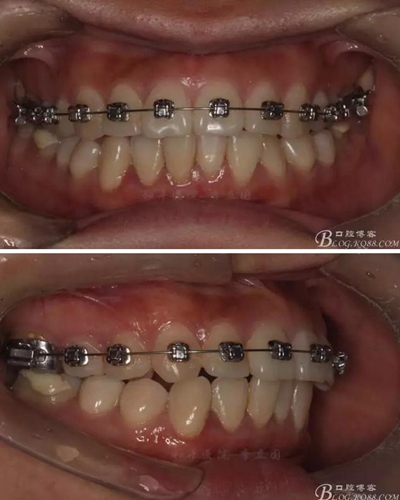

該病例主要為17、27頰側(cè)位同時(shí)伴有伸長(zhǎng),當(dāng)然種植支抗可以解決,但還有簡(jiǎn)單實(shí)用的辦法嗎?如圖,在橫腭桿遠(yuǎn)中延伸出牽引鉤,位置盡量遠(yuǎn)離合平面,7粘舌側(cè)扣,牽引力的方向?yàn)閴旱图吧嘞?,下圖為兩個(gè)月的效果,17已到位,27還未到位。